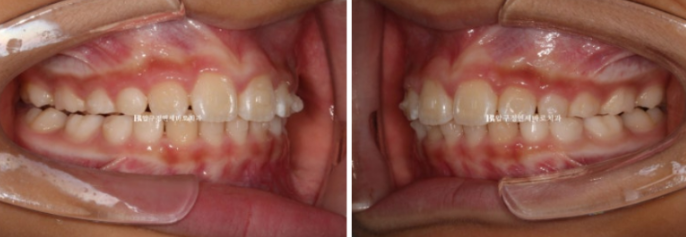

23.04

가장 먼저 보이는 것은 앞니 사이가 벌어진 것 이지만

이 벌어짐은 송곳니가 나오면서 모이기도 하기 때문에 큰 문제는 아닙니다.

그보다는 윗니가 아랫니를 많이 덮어 아랫니가 잘 보이지 않습니다.

과개교합 이라고 합니다.

윗니 아랫니 중심선이 맞지 않는 중심선 불일치도 보입니다.

옆에서 보시면 윗니 돌출이 심해보입니다.

하지만 골격 분석을 해보면 아래턱이 작아서 그렇게 보이는 것 입니다.

입천장은 좁고 앞니는 삐뚤합니다.